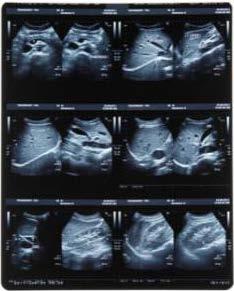

SONOGRAFÍA ABDOMINAL

Dra. Paola Pozo Rojas

P. 94